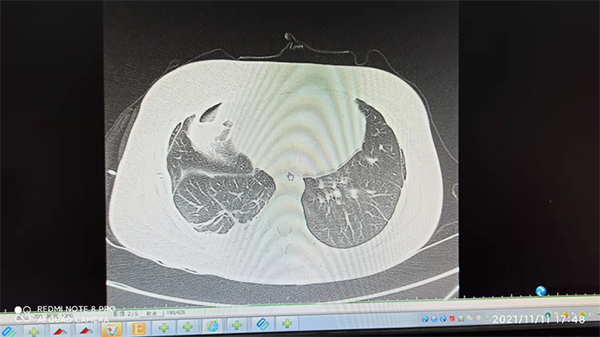

自入院那天起,这位患者的病情一直牵动着全科医护人员的心,周云芝主任和医护团队深知,该患者病情棘手,治疗难度大,但大家心往一处想,拧成一股绳,在难题面前毫不退缩。周云芝主任、高永平主治医生、付怀秀医生每天早上准时来到病房查房,认真细致查体,详细询问病情,反复向家属叮嘱饮食和护理注意事项。因为长期病情反复,患者心理压力很大,高永平主治医生和付怀秀医生经常给患者进行心理疏导,消除不良情绪,培养积极乐观的生活态度。最终,科室采用独特的堵漏方法成功为患者封堵了瘘口,让患者重获新生,能够自信的面对朋友和家人,回归到正常人的生活。

术后